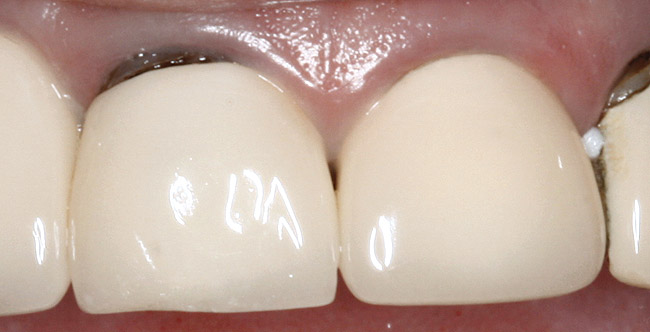

The clinical guideline of 4 mm—consisting of 1.5 mm of tooth structure and 2.5 mm biologic width1,3—is, therefore, the minimum limit for tooth structure above the alveolar bone (Figure 5). If this parameter cannot be met, there are two options for obtaining this threshold. One option is surgical crown lengthening,7,8 and the other is forced orthodontic eruption.9 The choice between each option should be made based on the effect each procedure will have on the esthetics of the case, the crown-to-root ratio, and whether osseous surgery will create a furcation involvement on the adjacent teeth (Figure 6). Esthetic considerations will be addressed later. In terms of crown-to-root ratio, there are two guidelines that exist for determining the minimum ratio (Figure 7). One is the classical 1:1 presented by Penny.10 The second, for maxillary anterior teeth, is 12 mm to 13 mm of tooth with 8 mm to 9 mm of root in bone and 4 mm coronal to the bone, as presented by Spear.1 If all of these criteria for tooth structure are met, then the tooth should be considered an acceptable candidate for retention and restoration. Also, if insufficient tooth structure exists, the required tooth structure can be obtained via forced orthodontic eruption or periodontal surgery provided that the esthetics and periodontal function of the tooth in question and the adjacent dentition are not compromised.